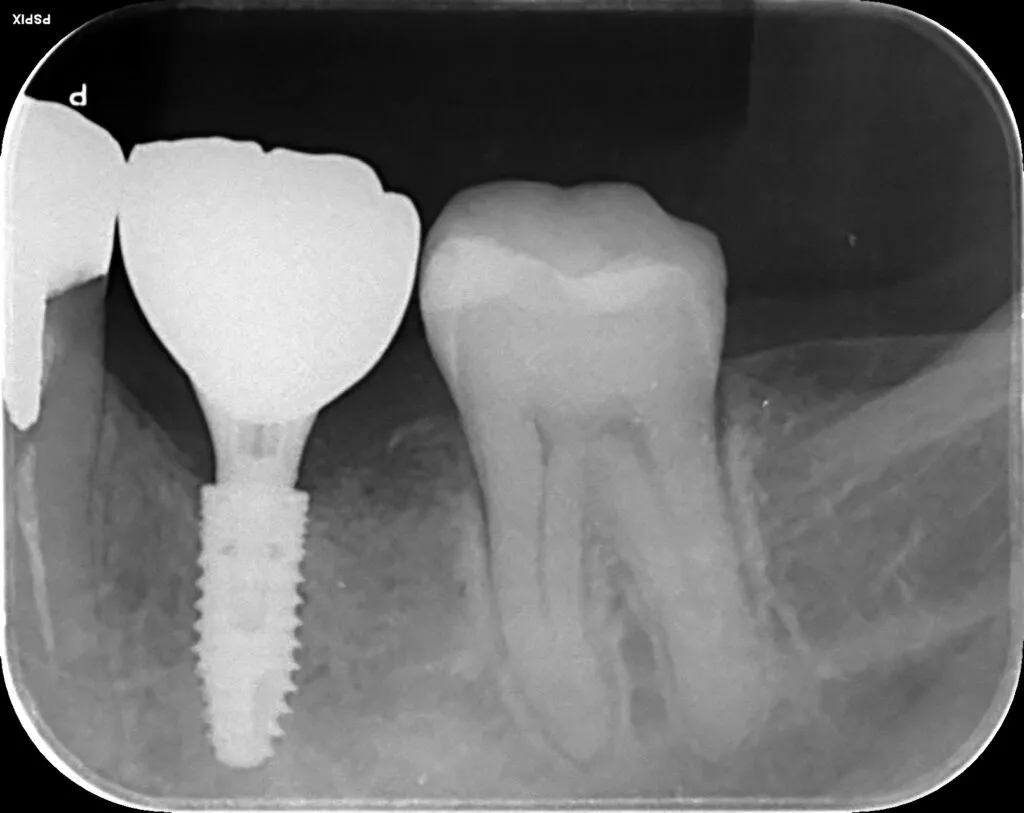

インプラント治療症例①

インプラント治療症例②

インプラント治療症例③

インプラント治療症例④

インプラント治療症例⑤

インプラント治療症例⑥

歯周病などで骨が少なくなった患者さんに対して行う、骨を再生させる処置(ソケットプリザベーション)